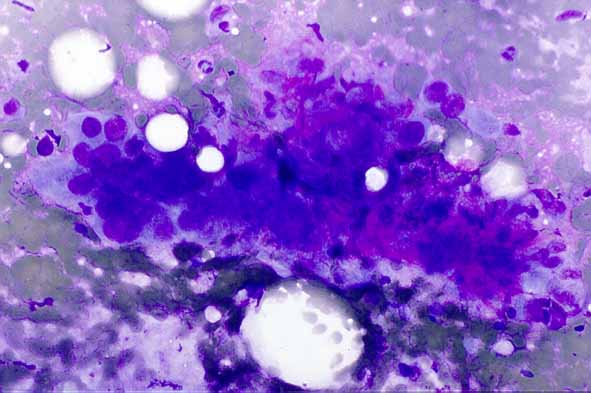

figura3.jpg (49542 bytes)

Figura 3. Metástasis de carcinoma anaplásico pulmonar.